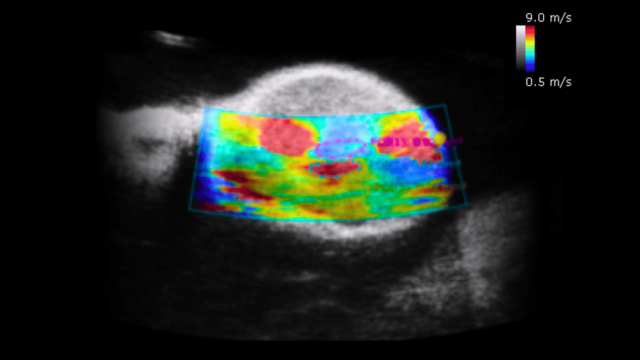

🫀 2. Hemodynamic Measurements in Small Animals Are Not Accurate with Clinical Systems

Clinical ultrasound is designed for imaging humans, not small animals with organs and vessels only millimeters, or even microns, wide. These systems typically operate between 2–15 MHz, which is far too low to resolve fine anatomical structures in mice or rats.

Preclinical ultrasound systems, on the other hand, operate at 15–50 MHz, enabling:

• High-resolution micro-anatomical imaging

• Precise visualization of vessels, valves, and soft tissues

• Improved ability to quantify subtle physiological changes

Without this resolution, many preclinical findings risk being missing or inaccurate.